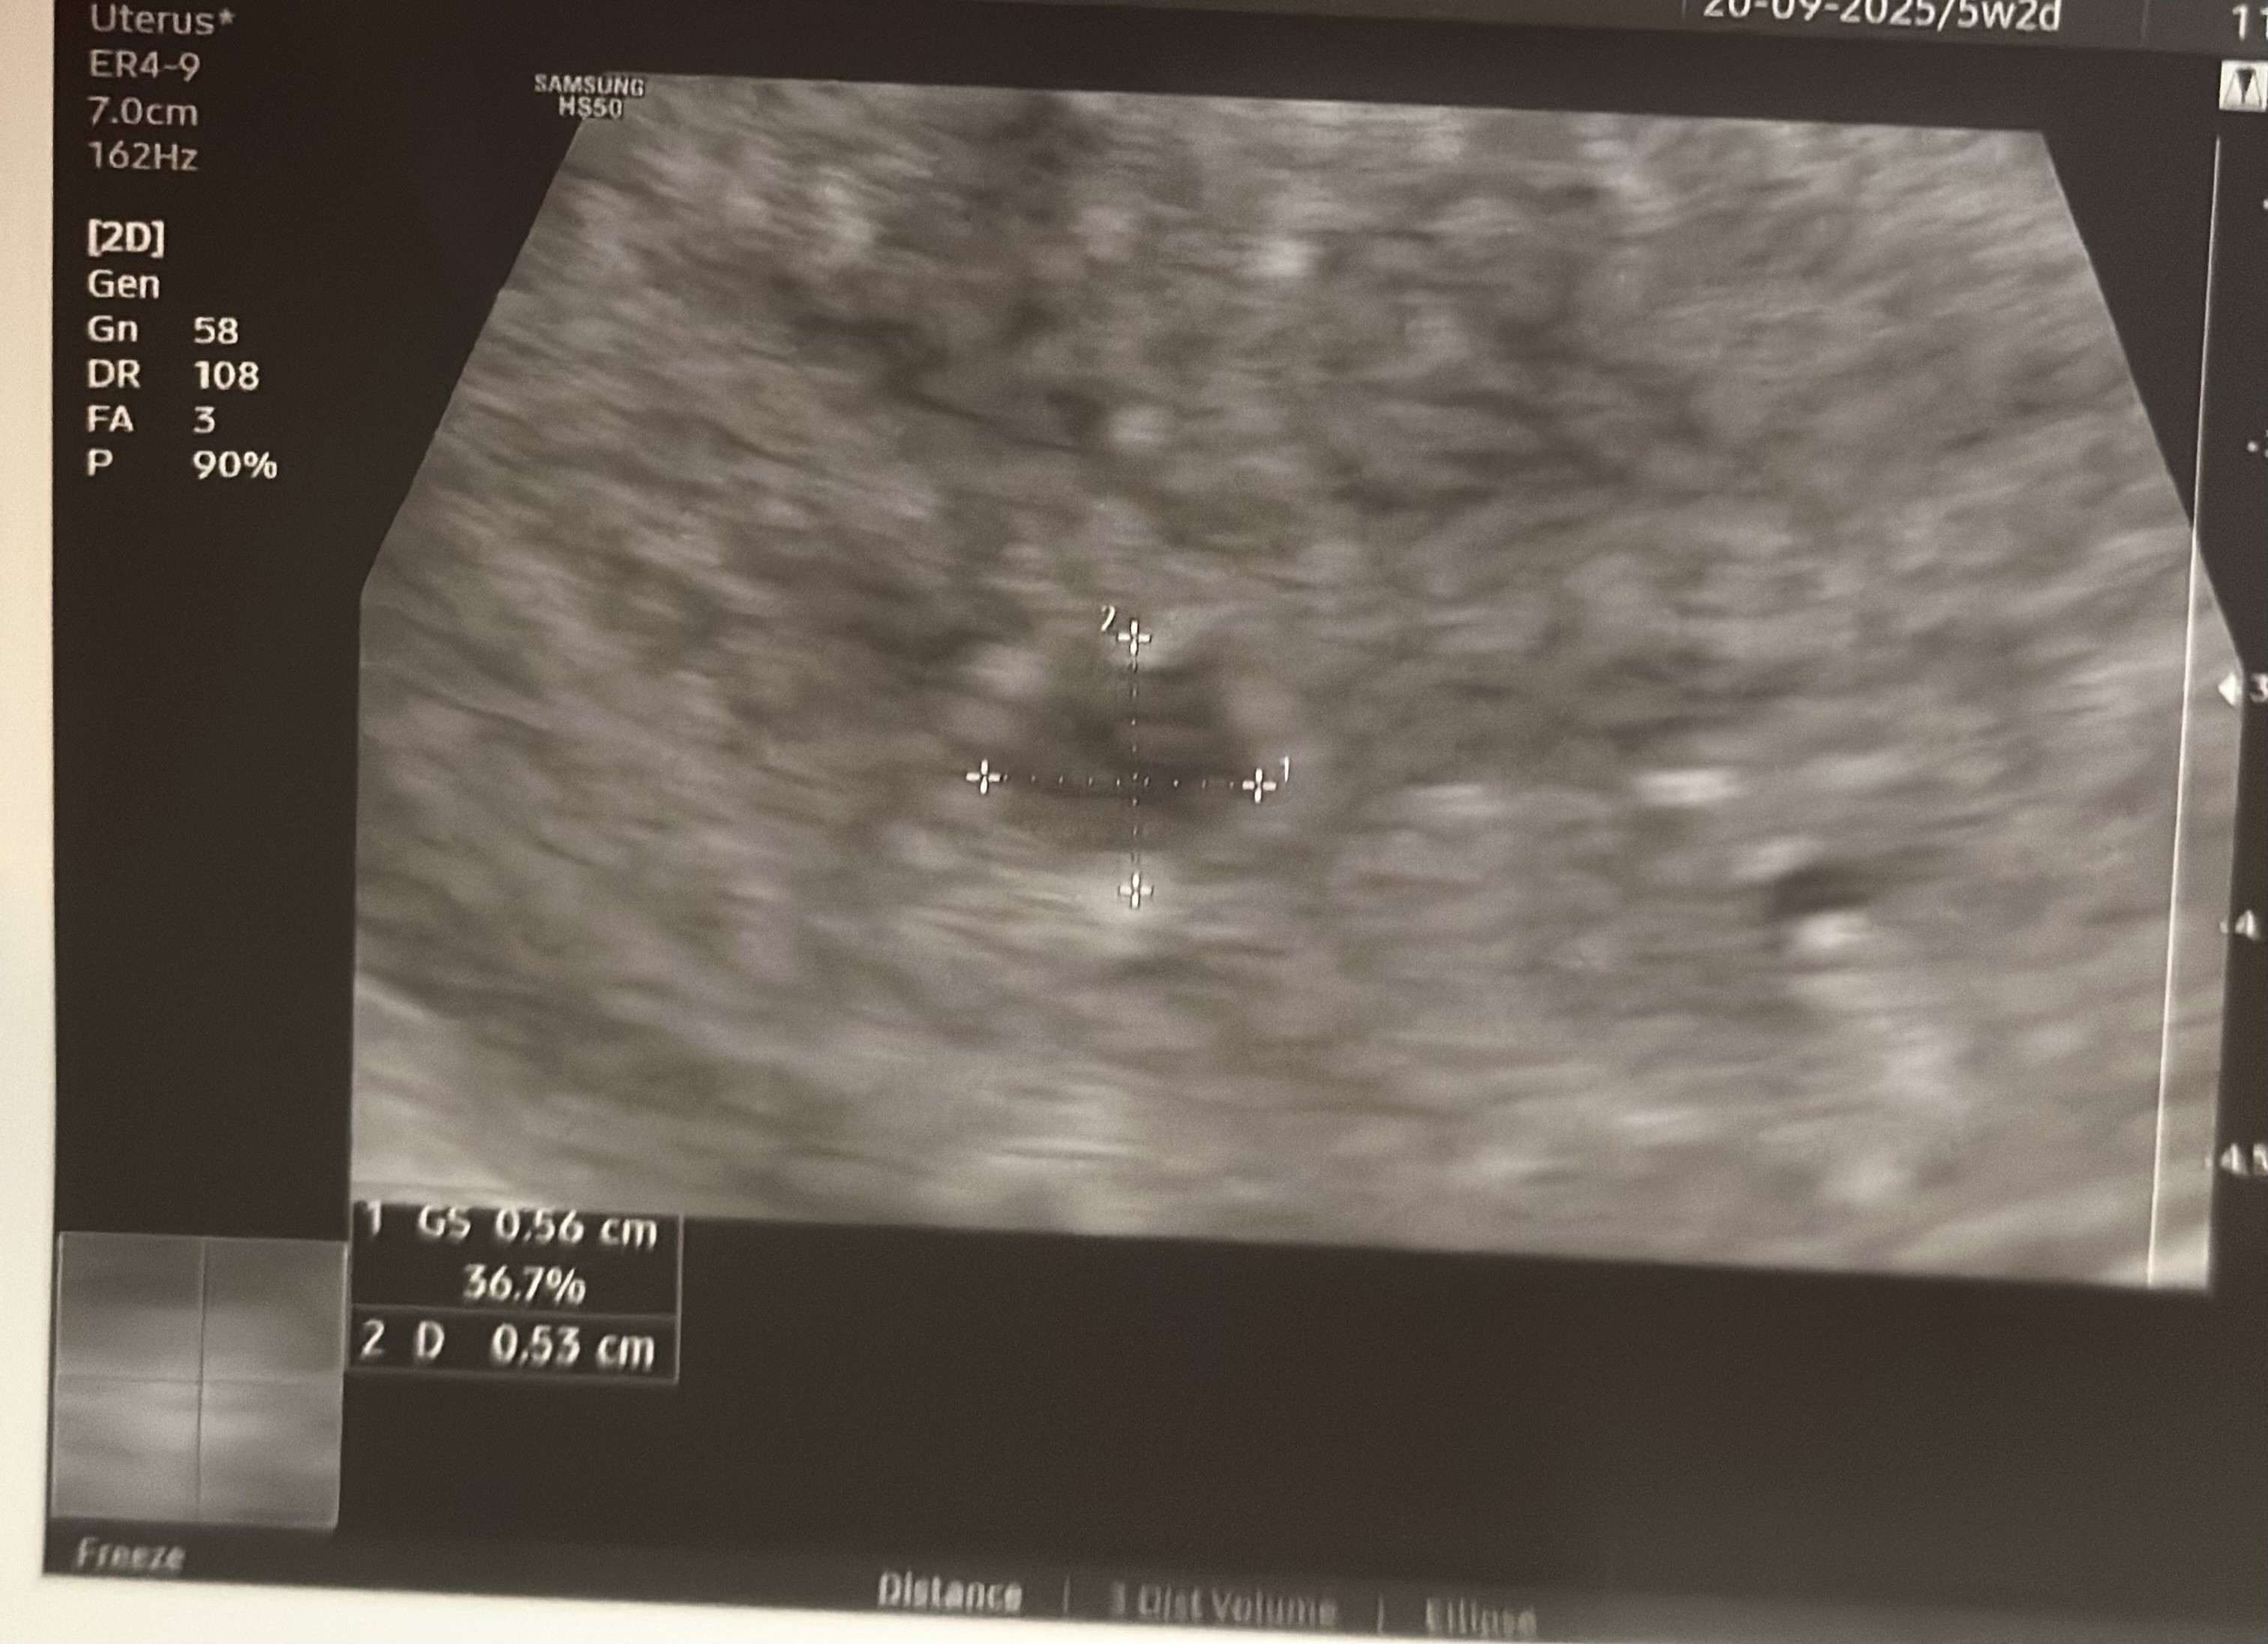

dopiero teraz zauważyłam jak zapytałaś o zdjęcie jakiej tragicznej jakości zdjęcie dostałam :o moja lekarka przyjmowała w innym gabinecie niż dawniej. możliwe że sprzęt tak kaprawy? czy po prostu pęcherzyk tak ekstremalnie mało widoczny?

mignęło mi zdjęcie 5mm pęcherzyka na innym wątku jakiejś dziewczyny i było super wyraźne.

Załączniki

• IMG_7599.jpeg

IMG_7599.jpeg

885,8 KB · Wyświetleń: 33